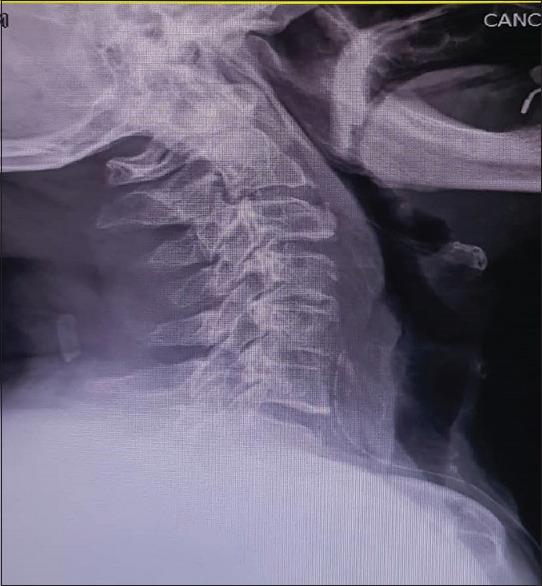

Diffuse idiopathic skeletal hyperostosis (DISH) also known as Forestier disease is a noninflammatory, systemic skeletal disease of unknown etiology. DISH is usually asymptomatic but may compress the posterior wall of the aero digestive tract and lead to dysphagia, globus, hoarseness, stridor, dyspnea, and neurological problems. Although dysphagia is not uncommon among the presenting symptoms of DISH but dysphonia and stridor are rarely reported. We report a 68-year-old man who presented with a history of progressive dysphagia over 1 year and recent dysphonia and stridor secondary to cervical osteophytes. We discuss the symptoms, radiological features, and management of this uncommon case of DISH in conjunction with review of literature.

摘要

弥漫性特发性骨肥厚(DISH),也称为福里斯特尔病,是一种病因不明的非炎症性全身性骨骼疾病。DISH通常无症状,但可能压迫上消化道后壁,导致吞咽困难、咽部异物感、声音嘶哑、喘鸣、呼吸困难和神经问题。虽然吞咽困难在DISH的症状中并不少见,但声音嘶哑和喘鸣很少被报道。我们报告一名68岁男性,有1年多进行性吞咽困难病史,近期因颈椎骨赘出现声音嘶哑和喘鸣。我们结合文献复习讨论了这例罕见的DISH病例的症状、影像学特征及治疗。